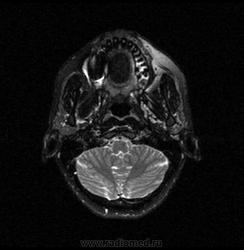

06.06.2011 МРТ - головы и шеи.

Пацентка 36 лет, с жалобами на припухлось в околоушной области справа.

В глубокой доле  правой околоушной железы  на фоне неизмененной паренхимы зона  гетерогенного по Т2, гипоинтенсивного по Т1  с единичными гиперинтенсивными включениями.При контрастировании- накопление контраста диффузное неоднородное и по периферии.Рискну предположить злокачественное образование ( аденокарцинома) с низкой степенью злокачественности( есть капсула, экспансивный рост).Сильно не расстреливайте.

Проблема в том, что перед челюстно-лицевым хирургом стоит распространенность любого объемного процесса, в данном случае все упирается в возмможную травму лицевого нерва и конечно же с дальнейшим его парезом, а ведь женщина  еще молодая. Образование имеет тонкостенную оболочку, по структуре неоднородно, с наличием кальцината, при этом МР-сигнал от окружающих анатомических структур(как костных так и мышечных) не изменен, т.е. об инфильтративном росте речи не идет, в какой то степени доброкачественное. В конкретном случае лицевой нерв с ретромандибулярной веной просто несколько оттеснен.

По гистологии аденома околоушной слюнной железы, но после удаления пока сохраняется парез лицевой мускулатуры, возможно временный.